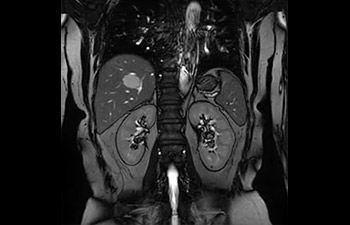

• Baanbrekende versnellingstechniek waarmee niet alleen sequenties versneld worden, maar uw gehele MRI-onderzoek. • Unieke implementatie waarmee 2D- en 3D-scans tot wel 50% sneller gemaakt kunnen worden met een nagenoeg gelijkwaardige beeldkwaliteit.1

• Kan gebruikt worden in alle anatomische contrasten en alle anatomieën.

1 In vergelijking met Philips-scans zonder Compressed SENSE. Resultaten van casestudy's bieden geen voorspellingen voor resultaten in andere gevallen. Resultaten in andere gevallen kunnen variëren.